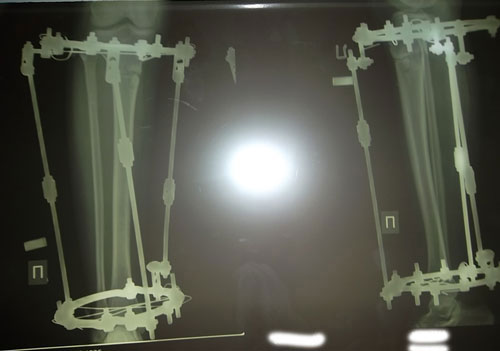

И прикрепляю фото моих ножек, очень уж схуднули они, нравится мне это :-)

Ножки выглядят обалденно, я бы от таких не отказалась!